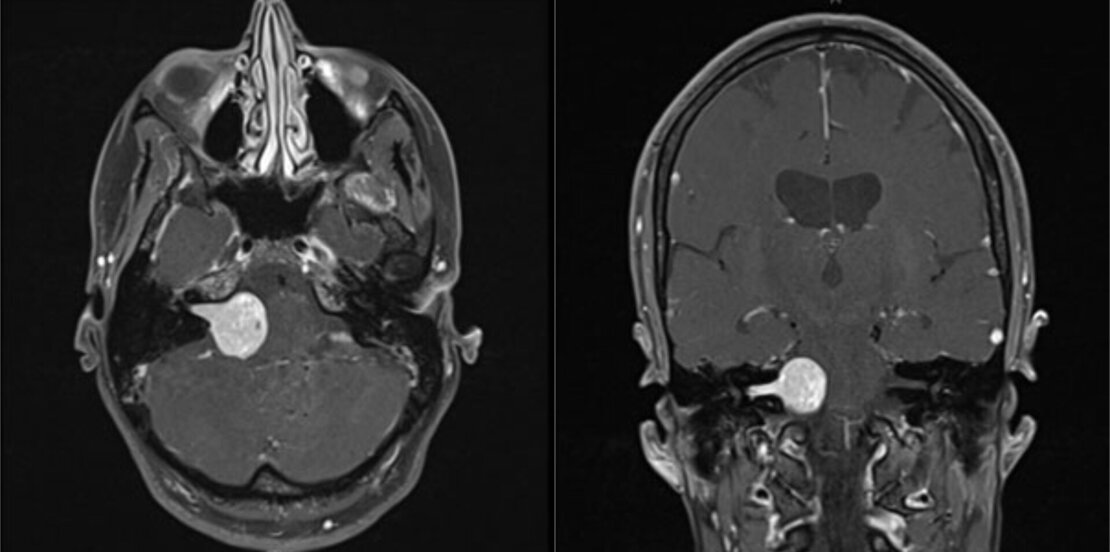

Vestibularisschwannome (Akustikusneurinome)

Diese gutartigen Tumore bilden sich aus den Hüllzellen des für das Gleichgewicht zuständigen Teils des VIII. Hirnnerven (Nervus vestibulocochlearis). Da dieser Nerv auch für die Übertragung der Impulse des Hörorgans sorgt, ist eine Hörstörung der betroffenen Seite oftmals Erstsymptom und darf insbesondere nicht mit einem Hörsturz verwechselt werden. Bei weiterem Wachstum kommt es dann - wie oben beschrieben - zu Gleichgewichts- und Gangstörungen.

Die Entscheidung kann letztlich nur im intensiven Gespräch mit dem Patienten fallen. Der operativen Therapie ist aber nach jetzigem Wissensstand insbesondere bei jungen, ansonsten gesunden Patienten mit beobachtetem Tumorwachstum oder aber neurologischen Ausfällen wie Hörstörung, Gleichgewichtsstörung, Gangstörung etc. der Vorzug zu geben. Außerdem besteht insbesondere bei kleinen Tumoren eine gute Chance, den Tumor unter Erhalt des Hörvermögens des betroffenen Ohres zu entfernen. Insgesamt ist das Risiko eines dauerhaften Hörverlustes ca. 5 %.